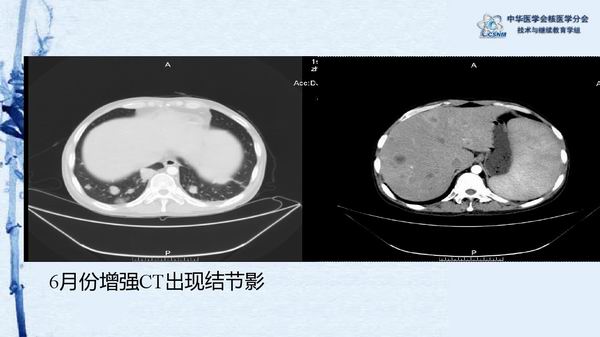

病例49:PET-CT显像诊断淋巴瘤相关噬血细胞综合征一例-【CSNM继教学组】程兵 郑州大学第一附属医院